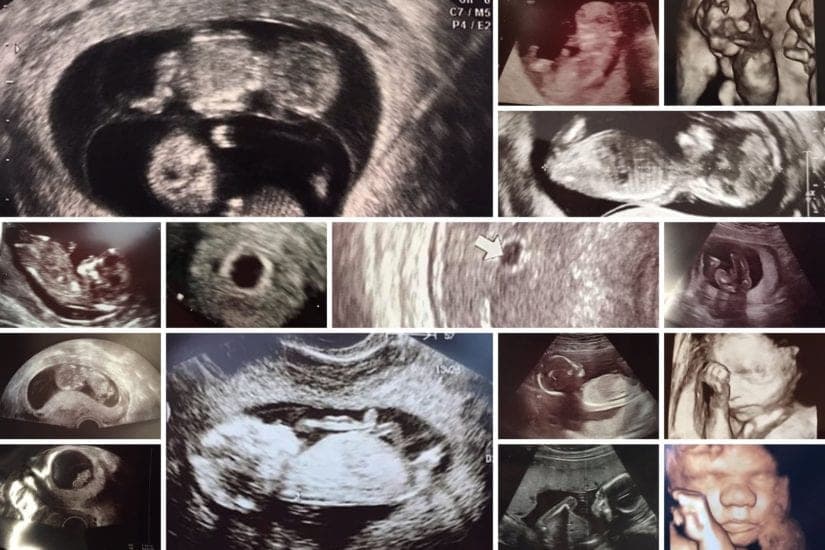

Die meisten werdenden Mamas (und auch die werdenden Papas!) freuen sich ganz besonders auf die Ultraschalluntersuchungen, bei denen ein Ultraschallbild gemacht wird. Diese Bilder machen das Wunder, das da in einem wächst so viel realer und greifbarer. Wer im Internet nach Ultraschallbildern sucht, der findet oft nur vereinzelt welche. Ich habe darum in meiner Community gesammelt und darf dir hier nun eine ganze Gallerie an Ultraschallbildern aus den verschiedenen Schwangerschaftswochen zeigen :)

Ultraschallbilder aus dem 1. Trimester (1. SSW bis 12. SSW)

Im ersten Trimester sind die Ultraschallbilder meist noch schwer zu deuten. Oft erkennt man in den letzen Wochen des ersten Trimesters gut den Körper, den Kopf und die Gliedmaße. Das Geschlecht kann man in dieser Zeit meist noch nicht erkennen.

Ultraschallbilder aus dem 2. Trimester (13. bis 28. SSW)

Im 2. Trimester bekommt man oft die schönsten „Ganz-Körper“ Ultraschallbilder. Das Baby ist nun so groß, dass man alles gut erkennen kann und noch nicht zu groß, so dass es noch ganz auf das Bild passt. In dieser Zeit lässt sich meist das Geschlecht bestimmen, wobei manche Babys es einfach nicht preis geben wollen und sich immer so drehen, dass man nichts erkennen kann.

Ultraschallbilder aus dem 3. Trimester (29. bis 40. SSW)

Im dritten Trimester der Schwangerschaft ist das Baby so groß, dass es nicht mehr komplett auf ein Ultraschallbild passt. Nun kann man wunderbare 3D-Ultraschalle des Gesichts machen. In diesem Semester nehmen die Babys nochmal rasant zu und wer Glück hat, kann auf seinem Ultraschall schon erste Gesichtszüge erkennen.

Was genau man auf einem Ultraschallbild erkennen kann, hängt nicht nur von der Größe des Babys ab, sondern auch davon wie gut das Ultraschall-Gerät ist, mit dem die Aufnahme gemacht wurde. Auch auf den Ultraschallbildern hier kannst du sehen, dass die Qualität stark schwankt. In der Regel kann man gut den Kopf und RUmpf des Babys erkennen und auch die Gliedmaßen erkennt man selbst als Laie gut.